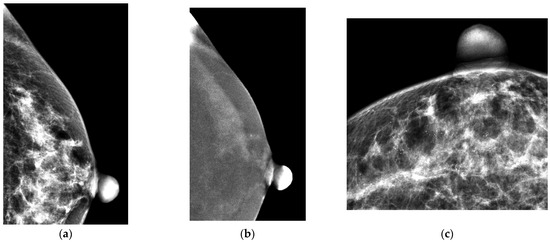

Figure 1

Histopathological Analysis of Vacuum-Assisted Breast Biopsy in Relation to Microcalcification Findings on Mammography: A Pictorial Review

by Jana Bebek, Nikolina Novak, Marina Dasović, Eugen Divjak, Čedna Tomasović-Lončarić, Boris Brkljačić and Gordana Ivanac

Biomedicines 2025, 13(3), 737; https://doi.org/10.3390/biomedicines13030737 - 18 Mar 2025

Mammography is an essential tool in breast screening, often revealing lesions that appear as microcalcifications with or without an associated mass. Decisions about biopsy requirements are guided by the BI-RADS system, aiming to confirm the histopathology of suspicious lesions while avoiding unnecessary procedures. [...] Read more.

Mammography is an essential tool in breast screening, often revealing lesions that appear as microcalcifications with or without an associated mass. Decisions about biopsy requirements are guided by the BI-RADS system, aiming to confirm the histopathology of suspicious lesions while avoiding unnecessary procedures. A vacuum-assisted breast biopsy (VABB) is a minimally invasive procedure for diagnosing breast abnormalities. Precise lesion targeting is ensured under stereotactic guidance, reducing the need for repeated procedures. Compared to traditional core needle biopsy (CNB) and fine-needle aspiration cytology (FNAC), it differs in using vacuum assistance to gather more tissue volume, increasing diagnostic accuracy and reducing the likelihood of histological underestimation. This is particularly crucial in cases where microcalcifications are the primary finding, as they are often the earliest signs of ductal carcinoma in situ (DCIS). Managing such findings requires precise diagnostic tools to differentiate benign from malignant lesions without subjecting patients to unnecessary surgical interventions. Building on several years of experience in our department, we have assembled a selection of ten interesting cases encountered in our clinical practice. Each case is documented with paired mammographic images and their corresponding image of histopathological findings, offering a comprehensive view of the diagnostic journey. These cases were selected for their educational value, highlighting the integration of imaging modalities, histopathological evaluation, and clinical decision-making. All cases underwent an extensive diagnostic workup at our facility. This compilation aims to provide valuable insights for both clinicians and researchers, offering a deeper understanding of advanced diagnostic techniques and their role in improving patient outcomes. Full article